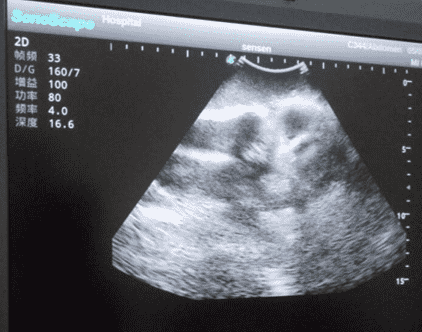

Knee Arthrocentesis Ultrasound Training Model

Model TYE1309

This model is an ideal choice for ultrasound-guided knee arthrocentesis training with true-to-life skin feel and touch, accurate anatomical structures as well as real clinical ultrasound images. Realistic resistance to needle tips and correct landmarks provide excellent hands-on experience.

· Anatomy: Femur, tibia, patella, joint cavity, synovial sac and synovial fluid, etc.

2)   Real clinical ultrasound images with clear anatomical structures like femur, joint cavity, etc.